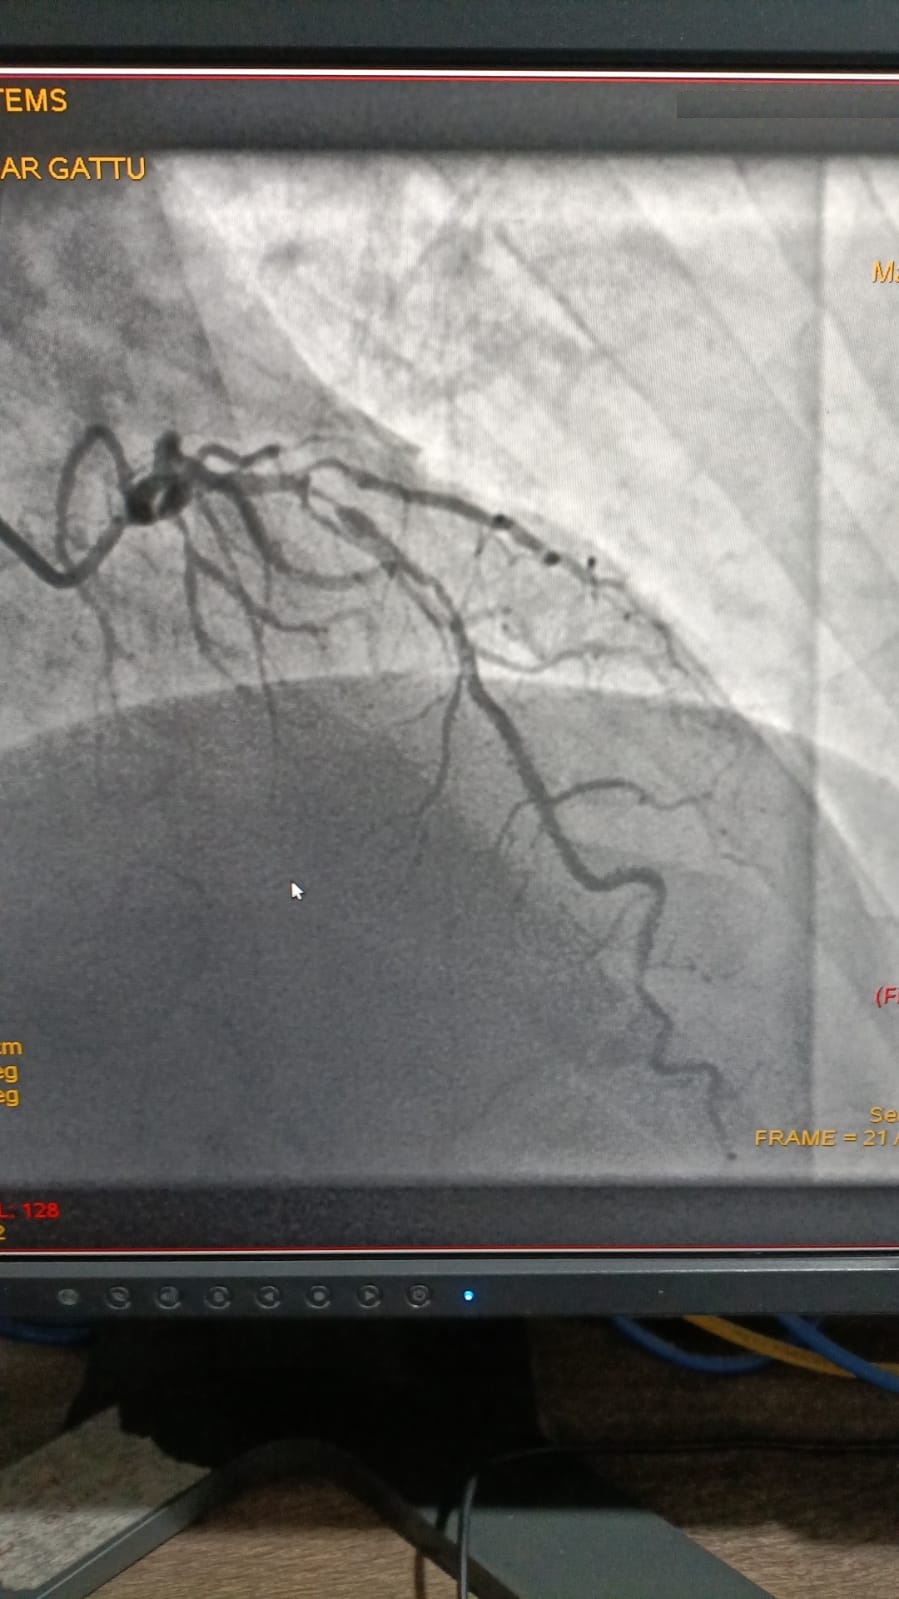

Left Coronary Artery